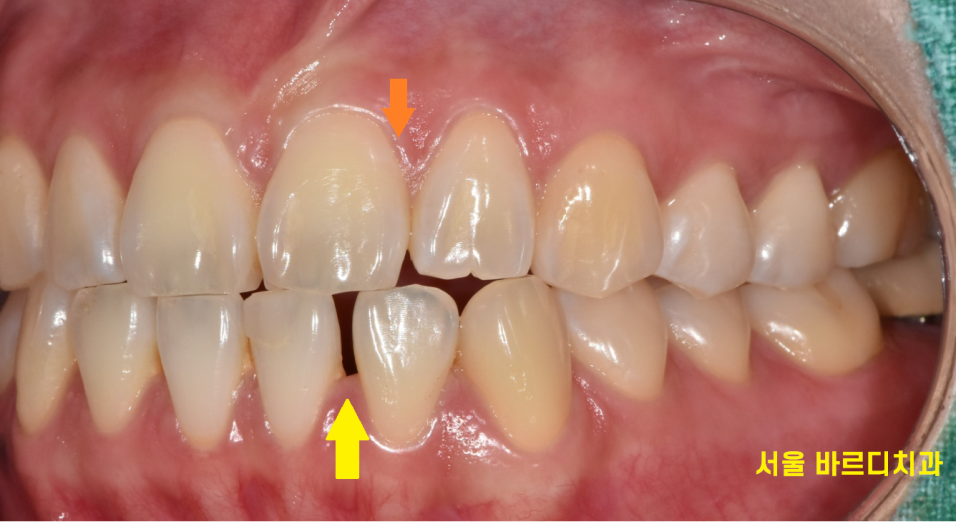

231116

벌어진 아래 앞니 공간이 싹 메꿔졌죠?

간혹 라미네이트로 치료하게 되면

치아가 커질까 걱정하시는 분들이 많습니다.

그렇지만 티가 나게 보철을 하면 안됩니다.

앞니 심미보철을 할 때는

티가 안나면서 내 주변 치아와 조화롭게 해야하는데요.

전체적인 이미지 변화를 보겠습니다.

3군데 정도 공간이 있었는데

감쪽같게 메꿔드렸습니다.